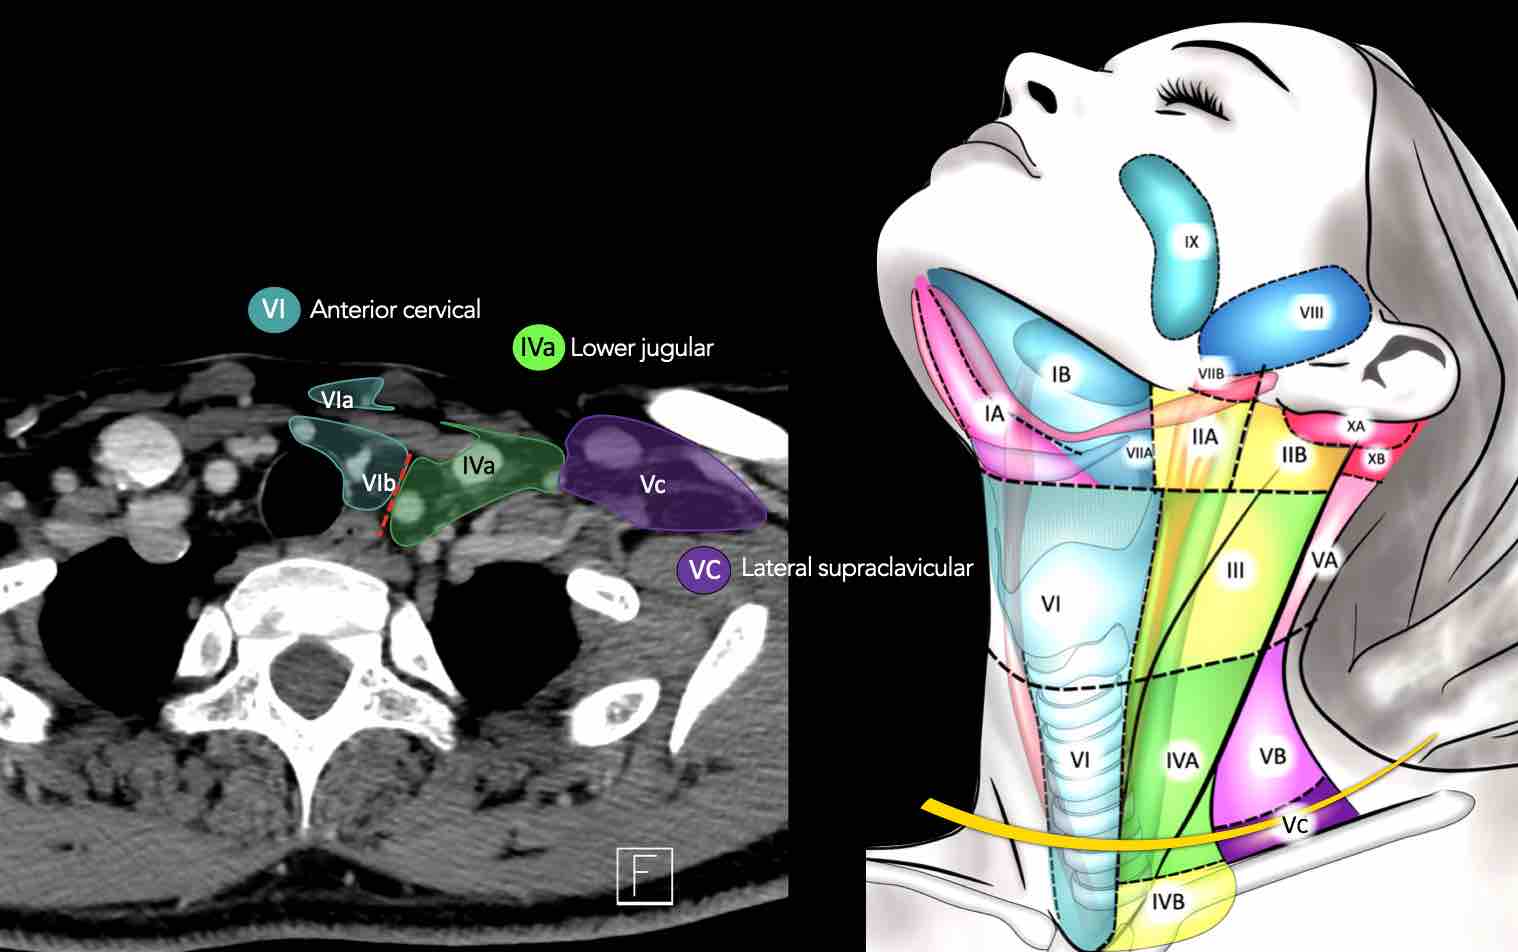

CT Scan Mặt Cắt Ngang (Axial CT)

Các lát cắt CT mặt phẳng ngang tương ứng với hình minh họa tổng quan.

Các lát cắt CT mặt phẳng ngang với hình ảnh chi tiết hơn.

Nhấp vào hình ảnh để phóng to.

Tầng Vc – Hố thượng đòn

Tầng này chứa các hạch thượng đòn bên nằm trong phần tiếp nối của các hạch tam giác cổ sau (tầng Va và Vb) từ các mạch máu cổ ngang xuống đến giới hạn được xác định tùy ý tại vị trí 2 cm phía trên cán ức.

Tầng này tương ứng một phần với vùng được gọi là hố thượng đòn.

Tầng Vc nhận các bạch mạch hướng tâm từ các hạch tam giác cổ sau (tầng Va và Vb) và thường liên quan hơn đến các khối u vòm hầu [1].